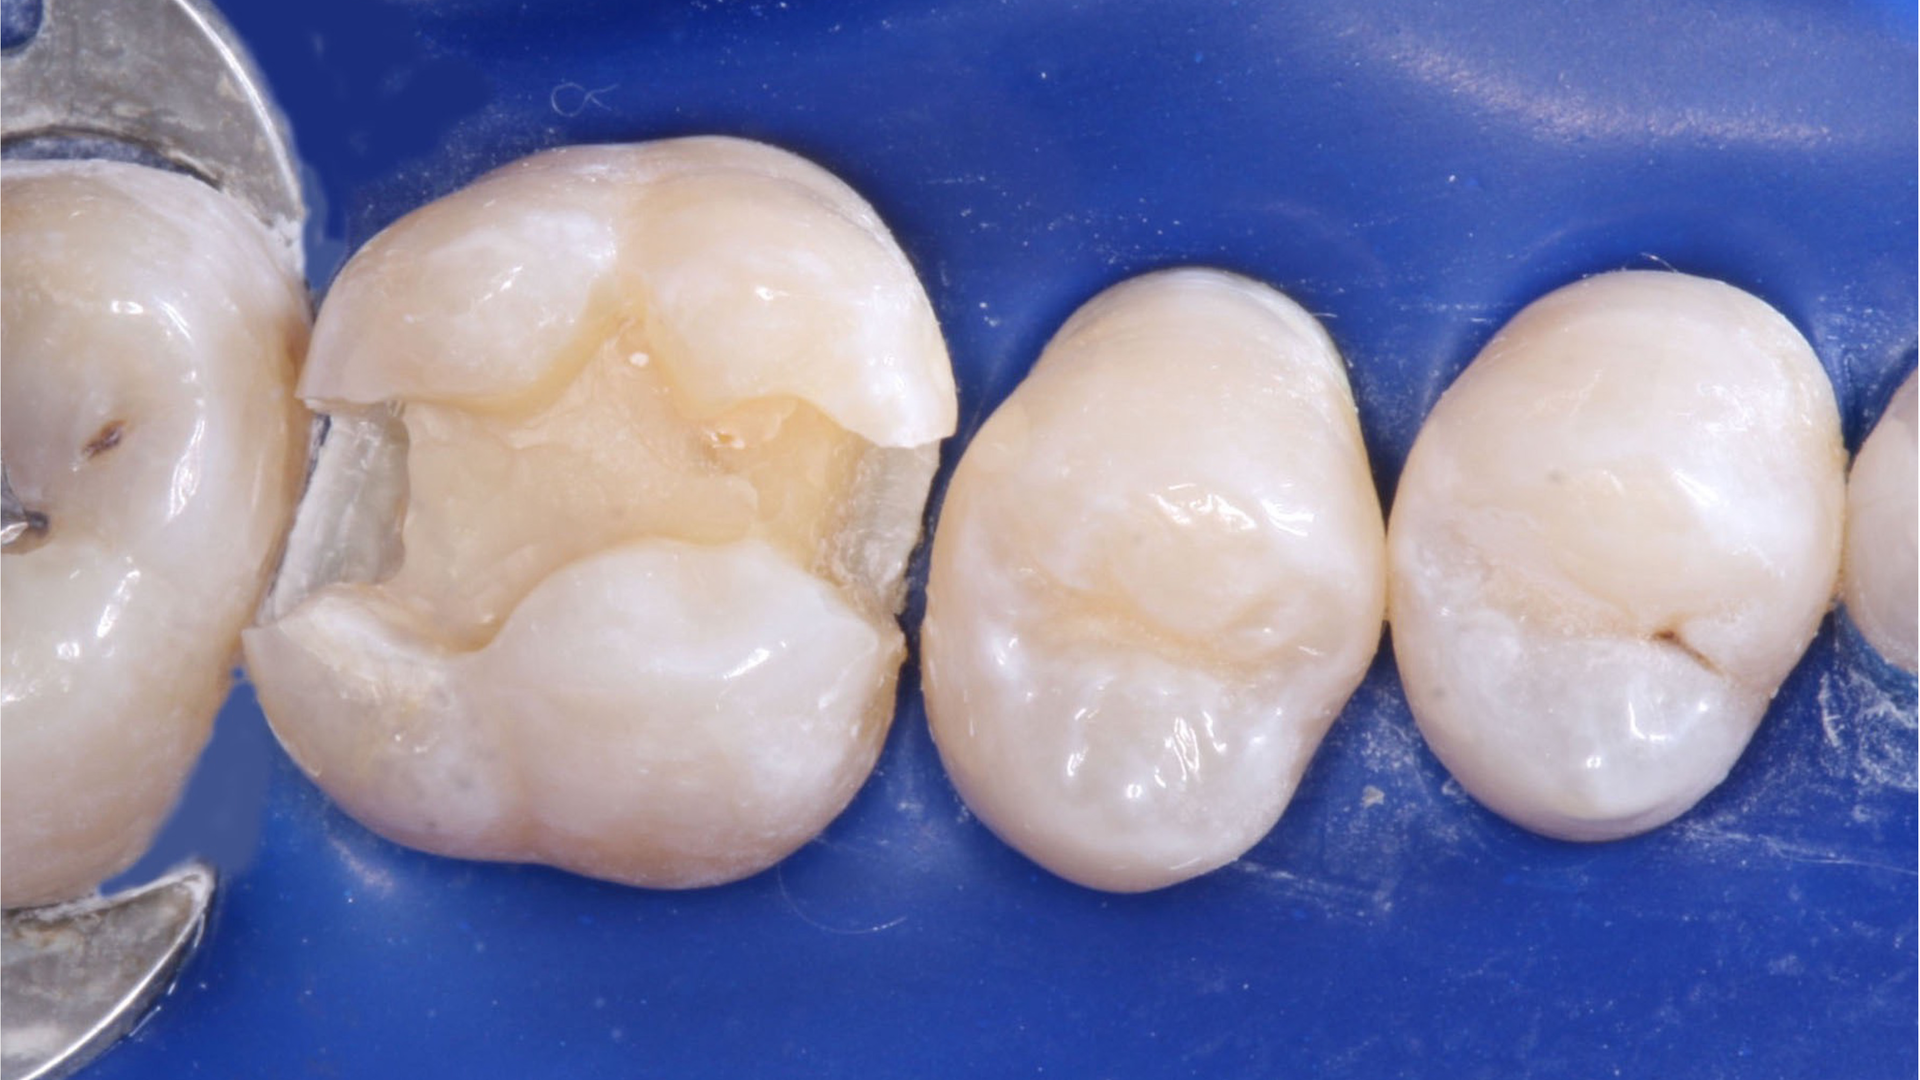

This is a well-known procedure, but it’s often confused with liners or bases. I have observed that almost all restorative dentists provide indirect pulp capping for their patients. The size and location of the dental pulp varies significantly depending on patient age and the extent of previous restorative treatment causing pulp response and reduction in pulp size (figure 1). When excavating caries, the ideal goal is to remove all observable caries without exposing the pulp. Often, the following situations occur in a typical day of practice: removal of the soft caries, dentin is hard to remove with an excavator, stained tooth structure remains, and the operator’s knowledge of dental anatomy and a radiograph indicate that a pulp exposure will occur if excavation is continued. An indirect pulp cap is placed on the deepest portions of the tooth preparation (figure 2).